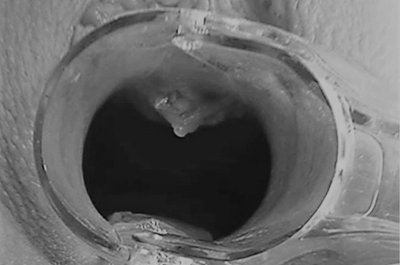

Ход операции

Врач вводит гиалуроновую кислоту непосредственно в точку G, которую предварительно определяет при пальпации, тем самым увеличивая ее упругость и амортизацию.